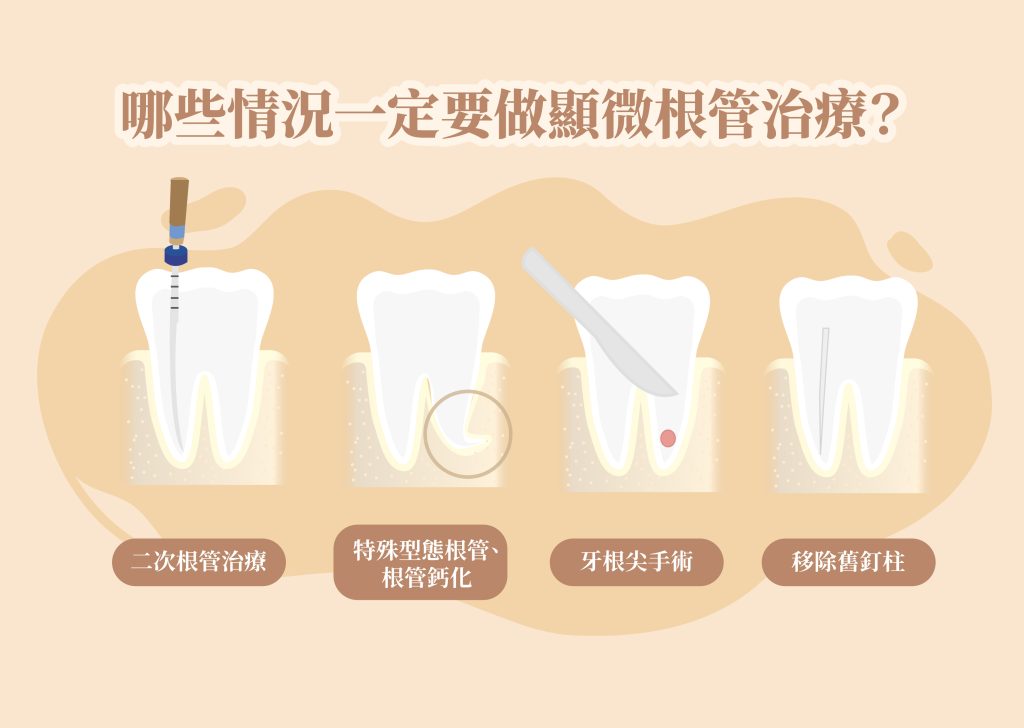

根管治療是處理嚴重蛀牙及牙髓感染的常見療程,目的是透過清除發炎或壞死的牙髓組織,幫助患者最大程度保留健康齒質,延長真牙的使用壽命。而當牙齒內部的根管系統複雜,例如根管彎曲、分岔細小、鈣化阻塞或曾接受過治療但仍反覆感染,且傳統肉眼操作可能很難徹底清潔感染組織時,就需要高倍率手術顯微鏡的幫助,透過「顯微根管治療」提升療程成功率。

上述情況僅供參考,實際狀況是否顯微根管治療還能救治,需由牙醫師仔細評估牙齒結構、神經管狀態與整體口腔條件。